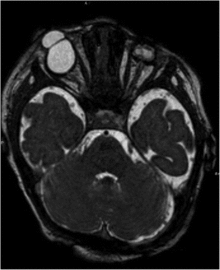

| Bilateral cryptophthalmos with microphthalmos in the left ocular globe and abnormal right ocular globe in a female infant with Fraser syndrome. | |

It is characterized by developmental defects including cryptophthalmos (where the eyelids fail to separate in each eye), and intersex development in the genitals (such as micropenis, or clitoromegaly) and cryptorchidism[3] Congenital malformations of the nose, ears, larynx and renal system, as well as developmental delays, manifest occasionally.[4] Syndactyly (fused fingers or toes) has also been noted.[5]